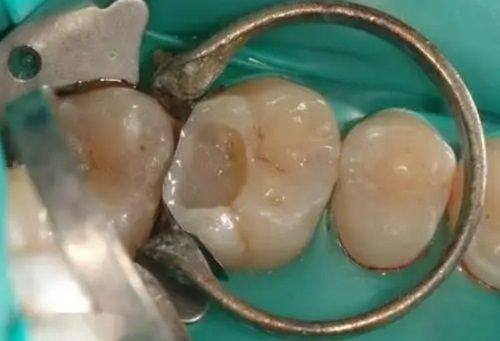

根管治疗:借助数字化X光机辅助精细诊断病灶,医生技术成熟,操作规范,能有效清除根管内的感染物质,缓解牙痛症状,较大程度保留患牙,治疗过程消毒严格,降低复发几率。